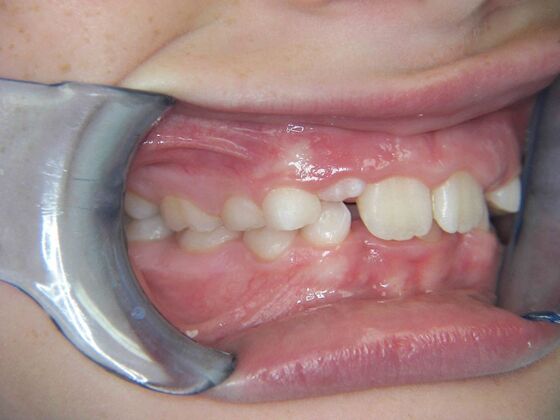

Patient is 9 years old and presents with 100% overbite and blocked out upper and lower lateral incisors. Both upper central incisors are palatally inclined causing a lack of space available for most anterior teeth. Advised her parents that she needs Phase I Interceptive Orthodontic treatment to provide room for all upper and lower front teeth. Phase I treatment was begun and finished, then began Phase II treatment shortly thereafter to finalize case. Removable retainer were fabricated for retention.